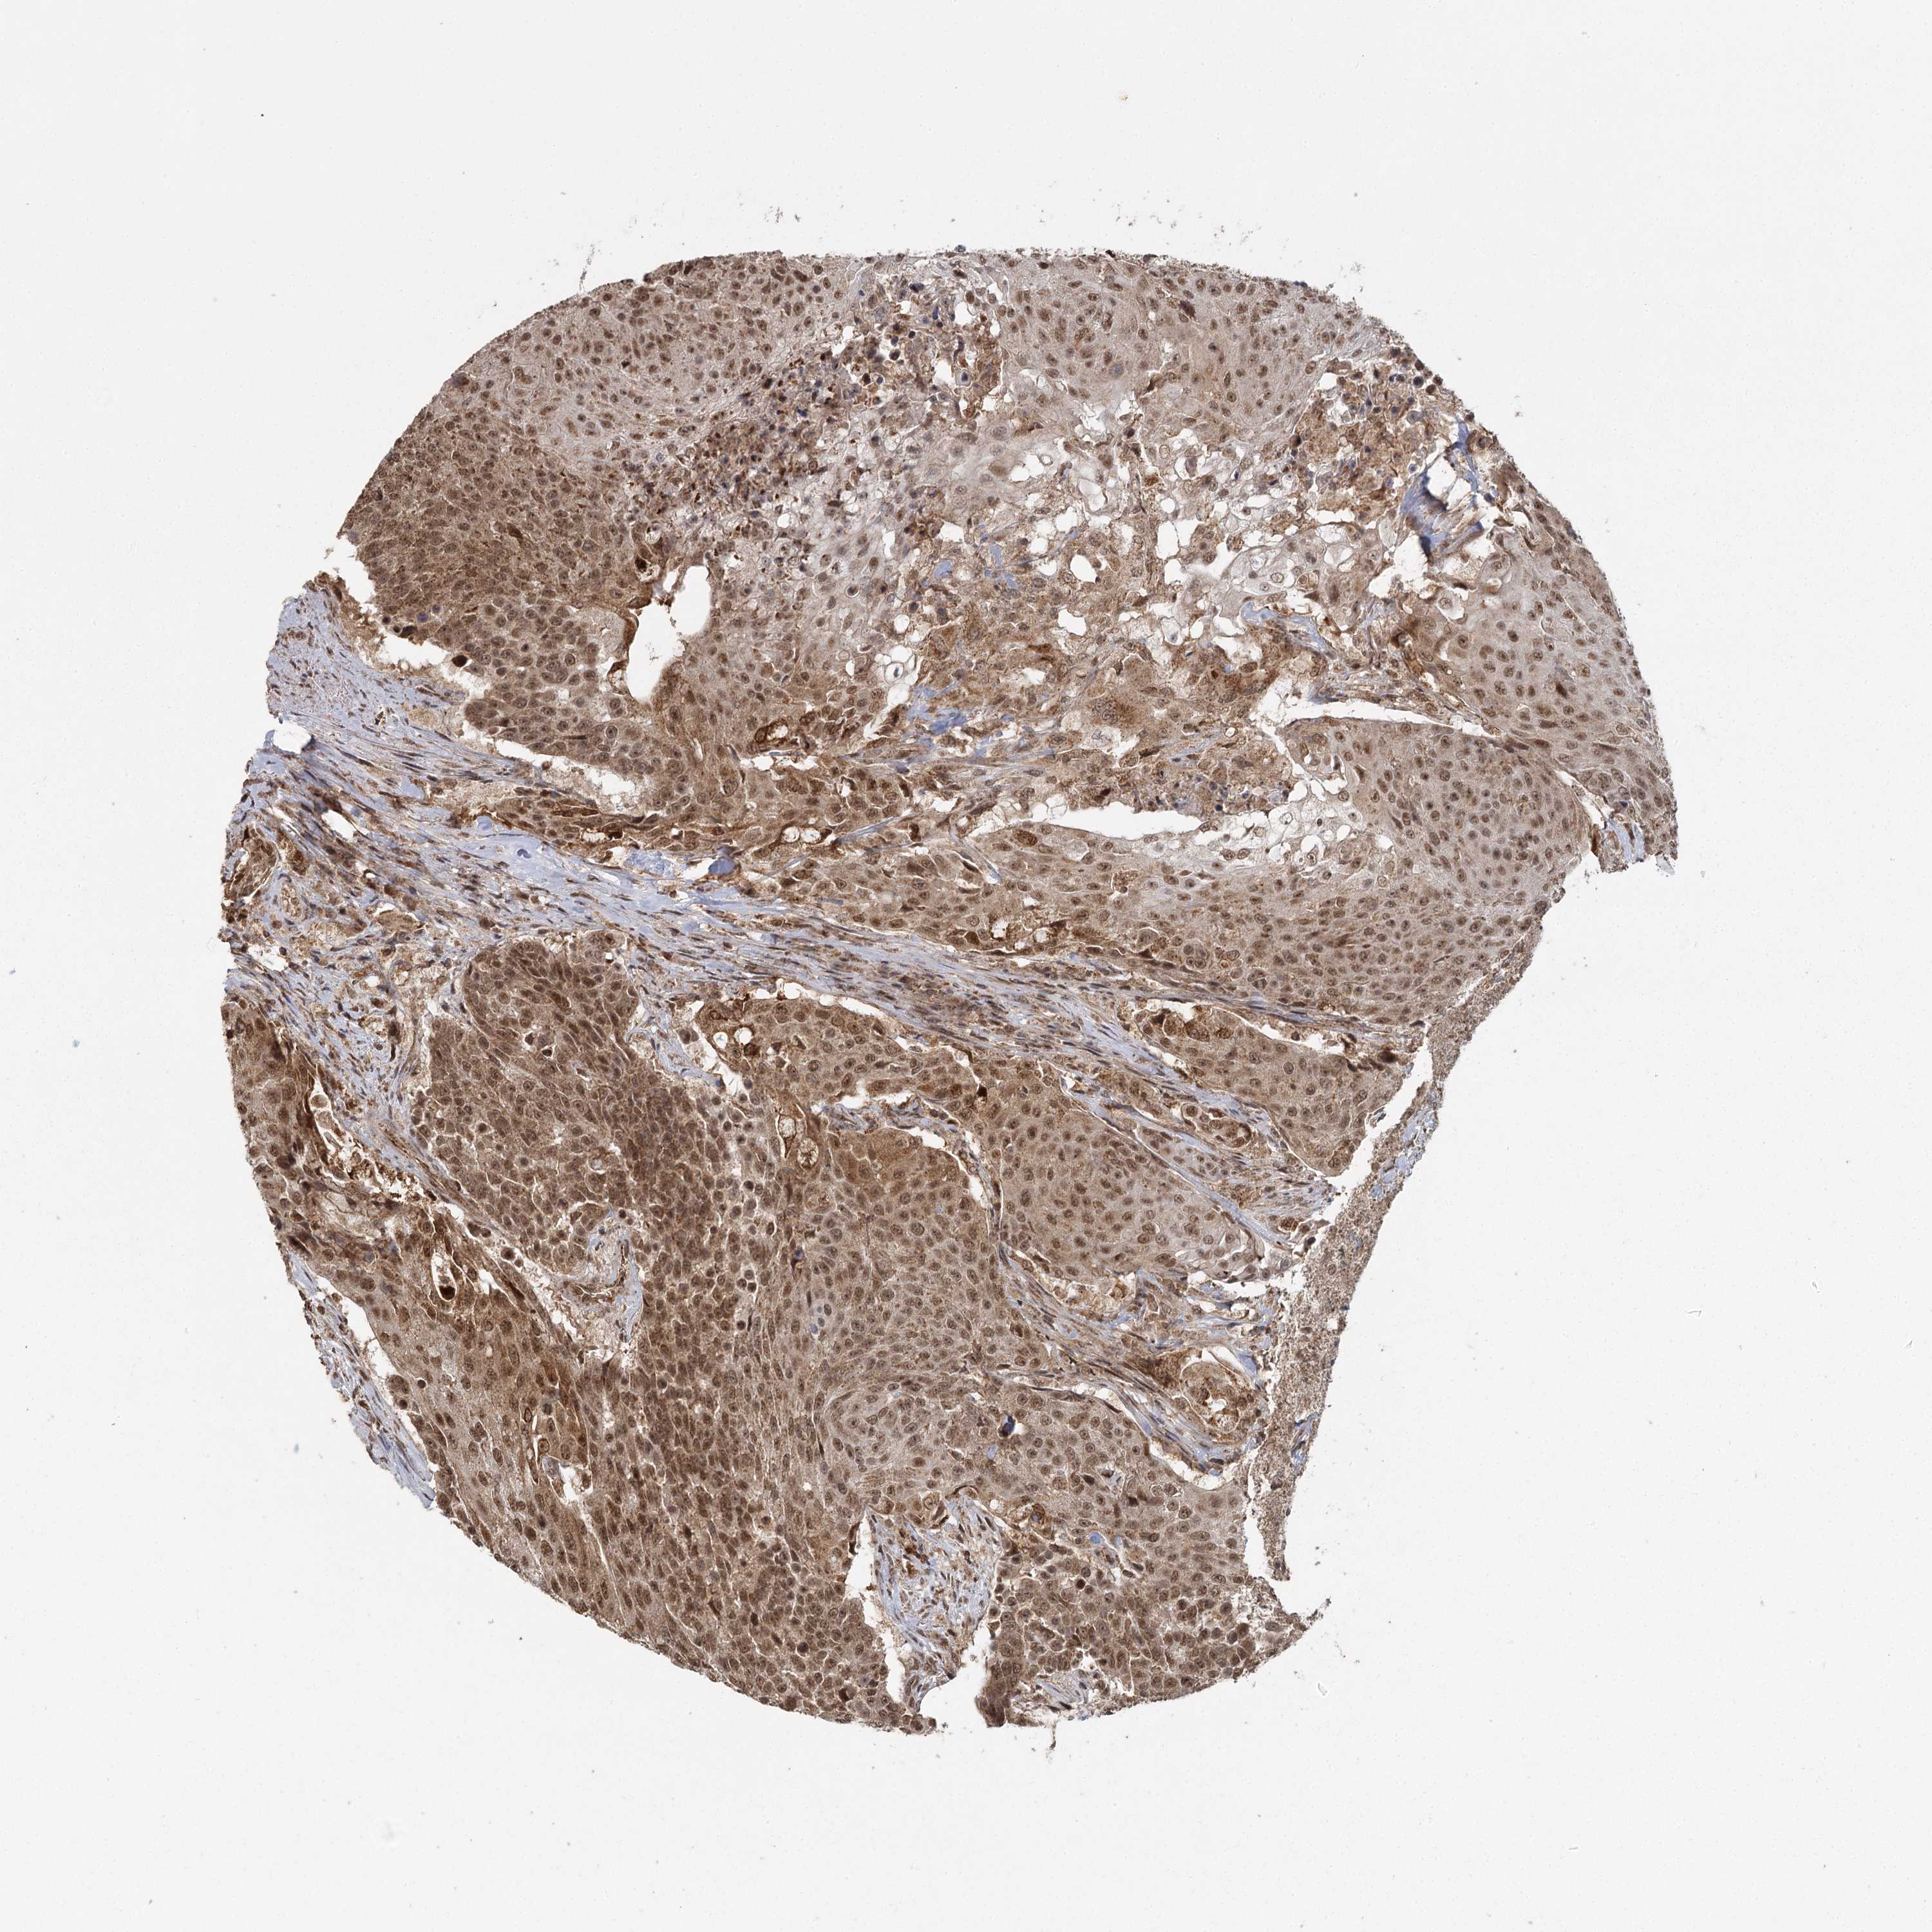

UROTHELIAL CANCER - Protein expressioni

A mouse-over function shows sample information and annotation data. Click on an image to view it in a full screen mode. Samples can be filtered based on level of antibody staining by selecting one or several of the following categories: high, medium, low and not detected. The assay and annotation is described here.

Note that samples used for immunohistochemistry by the Human Protein Atlas do not correspond to samples in the TCGA dataset.

Antibody stainingi

Antibody staining in the annotated cell types in the current human tissue is reported as not detected, low, medium, or high, based on conventional immunohistochemistry profiling in selected tissues. This score is based on the combination of the staining intensity and fraction of stained cells.

Each image is clickable and will lead to virtual microscopy that enables deeper exploration of all samples and also displays staining intensity scores, fraction scores and subcellular localization as well as patient and tissue information for each sample.

Antibody HPA037480

Staining

High

Medium

Low

Not detected

Intensity

Strong

Moderate

Weak

Negative

Quantity

>75%

75%-25%

<25%

None

Location

Nuclear

Cytoplasmic/membranous

Cytoplasmic/membranous,nuclear

Urothelial carcinoma, Low grade

Urothelial carcinoma, High grade

Urothelial carcinoma, NOS